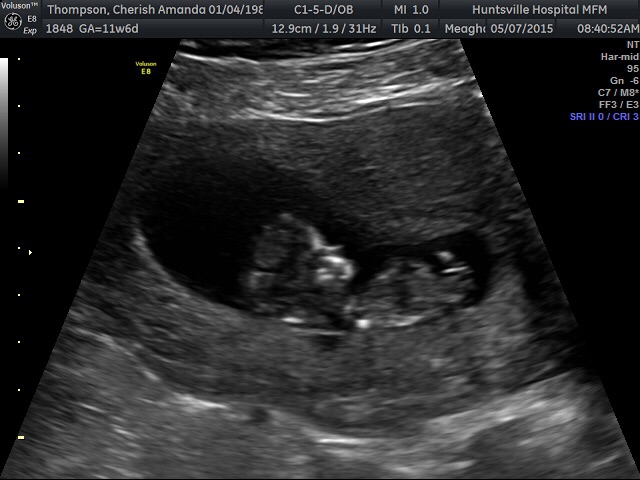

Had my NT ultrasound yesterday and everything looked great! Moving and flipping around! I'm 12 weeks 4 days according to the NT ultrasound, a couple days ahead of what I thought! So amazing!!!